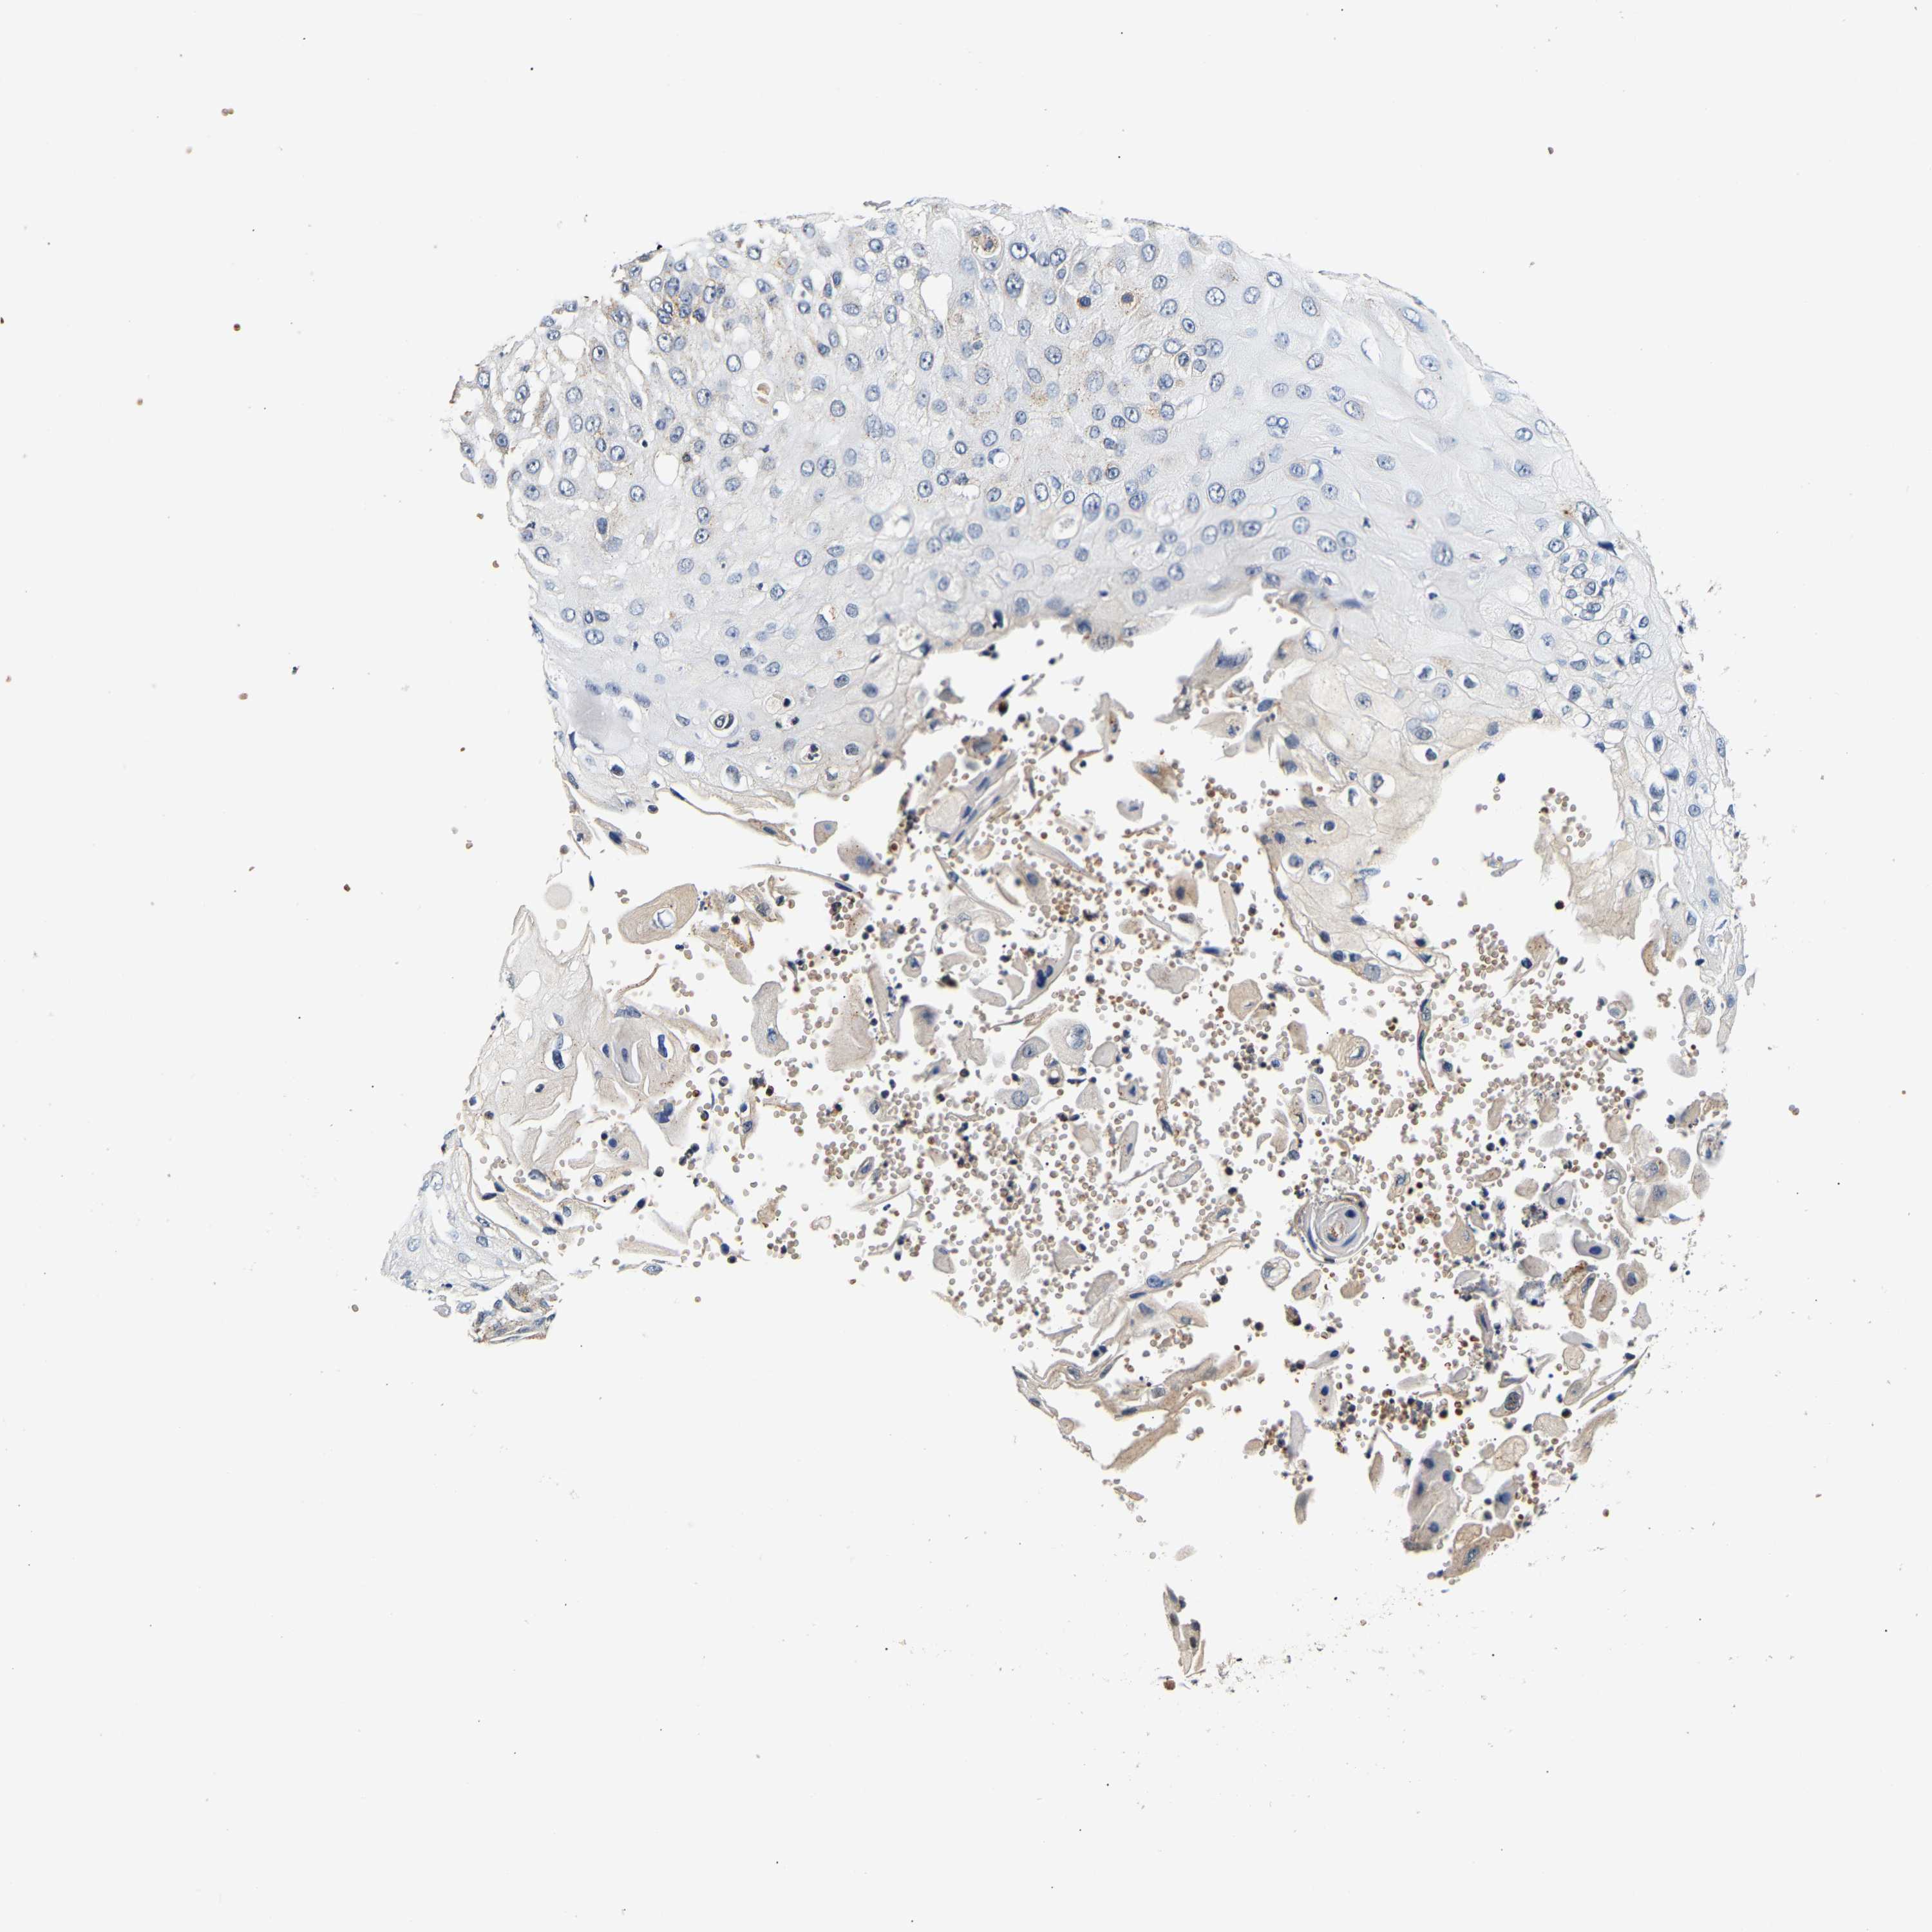

Basal cell and squamous cell cancer

SKIN CANCER - Protein expressioni

A mouse-over function shows sample information and annotation data. Click on an image to view it in a full screen mode. Samples can be filtered based on level of antibody staining by selecting one or several of the following categories: high, medium, low and not detected. The assay and annotation is described here.

Antibody stainingi

Antibody staining in the annotated cell types in the current human tissue is reported as not detected, low, medium, or high, based on conventional immunohistochemistry profiling in selected tissues. This score is based on the combination of the staining intensity and fraction of stained cells.

Each image is clickable and will lead to virtual microscopy that enables deeper exploration of all samples and also displays staining intensity scores, fraction scores and subcellular localization as well as patient and tissue information for each sample.

Antibody HPA019708

Staining

High

Medium

Low

Not detected

Intensity

Strong

Moderate

Weak

Negative

Quantity

>75%

75%-25%

<25%

None

Location

Nuclear

Cytoplasmic/membranous

Cytoplasmic/membranous,nuclear

Squamous cell carcinoma, NOS